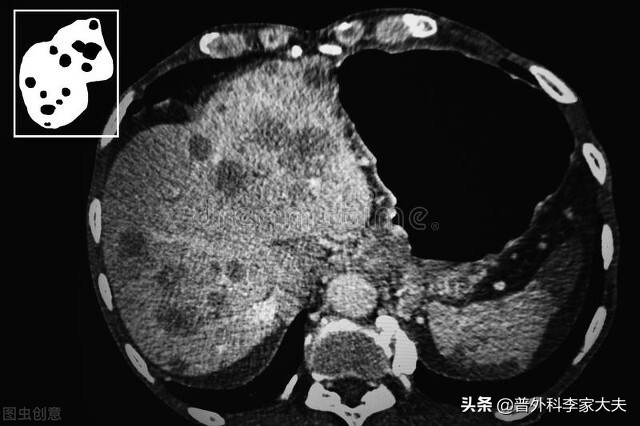

肝癌